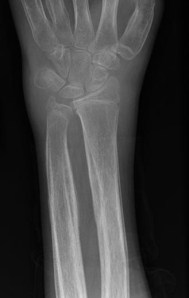

313) A 54 year old man is evaluated in your office for swelling of bilateral wrists and ankles. He also describes pain in his wrists and ankles as well as in the lower legs. Symptoms started 2 months ago and have been progressively worse. He reports limitation in walking because of extreme pain. He denies any stiffness. His past medical history is significant for chronic obstructive pulmonary disease for which he uses Tiotropium inhaler. He recently quit smoking but reports having smoked about 2 packs per day for 35 years. On physical examination, his vitals are within normal limits. Musculoskeletal exam reveals swelling and tenderness in bilateral wrists and ankles. There is an associated grade 3 clubbing in the fingers. There also tenderness all over the tibiae. Overlying skin is thickened and erythematous. An erythrocyte sedimentation rate is elevated at 30 mm/hr. An x-ray of his upper extremity is shown below:

Which of the following investigations should be ordered next?

D) CT Scan of the Chest